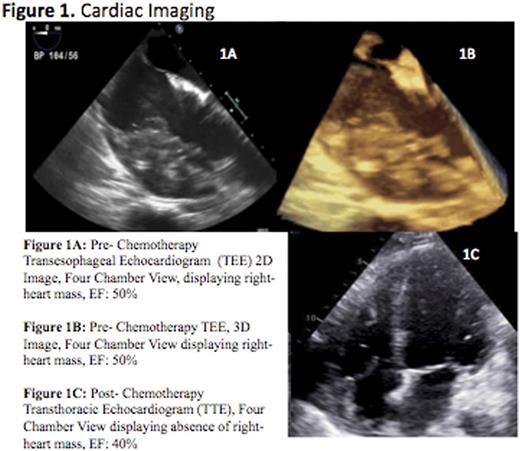

This is a case of a 72-year-old white man with past medical history significant for paroxysmal atrial fibrillation and known pulmonary, renal, and cutaneous sarcoidosis who presented with palpitations, dyspnea on exertion and lightheadedness for two-weeks. He was evaluated by his cardiologist who recommended an elective atrial fibrillation radiofrequency ablation (RFA). Prior to the planned procedure a transesophageal echocardiogram was performed which revealed a large tissue density within the pericardial space, adjacent to the free wall of the right ventricle and right atrium, and invading the myocardium with extension through the interatrial septum (Figure 1). The RFA was aborted and the patient was admitted for further evaluation of the new cardiac mass, initially suspected to be cardiac sarcoidosis.

Our patient was observed closely in the cardiac intensive care unit throughout the duration of chemotherapy due to the high risk of fatal arrhythmia, tamponade, perforation and heart failure. Interim restaging, confirmed complete remission of the intracardiac mass. His post chemotherapy TTE demonstrated a slight reduction in ejection fraction (Figure 1). He received a total of three cycles of EPOCH-R and remained hemodynamically stable within the hospital. No further chemotherapy was given due to a decline in the patient's performance status.